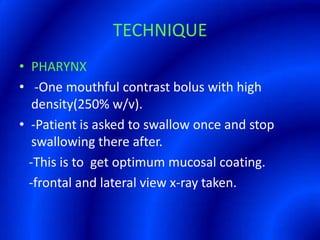

This document provides information about a barium swallow procedure. It begins with an introduction and overview of the embryology and anatomy of the pharynx and esophagus. It then describes the procedure itself, including preparation, technique, views obtained, and indications. Specific conditions that may be examined include pharyngeal and esophageal webs, foreign body impaction, scleroderma, dysphagia, mediastinal masses, and carcinoma. Diagrams are provided to illustrate normal anatomy and various pathological findings.